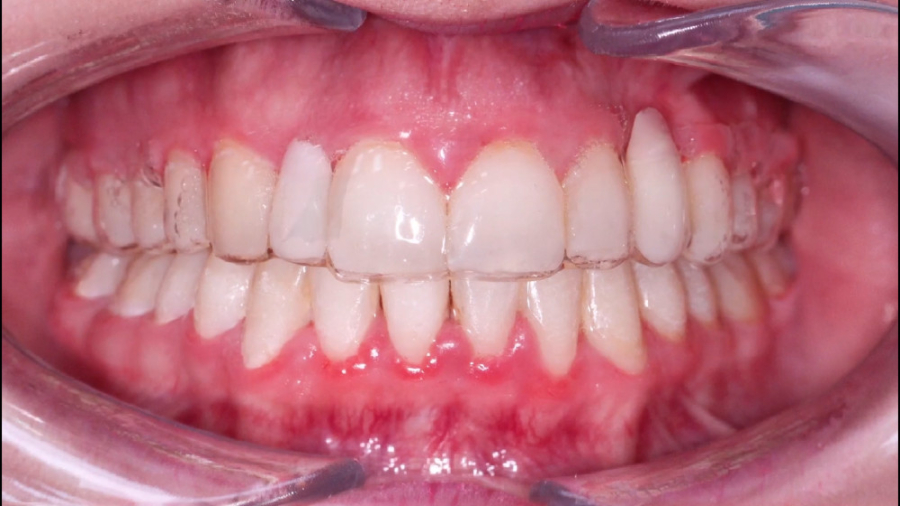

قبل و بعد از ارتودنسی اپن بایت | دکتر داودیان

1515 بازدید